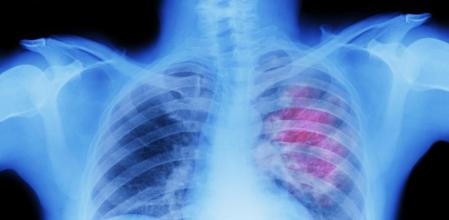

Con casi 31.000 nuevos diagnósticos previstos en 2022 y unas 22.000 muertes anuales, el cáncer de pulmón es el tercero en incidencia y el primero en mortalidad en España, según datos de la Sociedad Española de Oncología Médica (SEOM). Su elevada mortalidad se atribuye a que entre el 75% y el 80% de los casos se diagnostican demasiado tarde para poder extirpar los tumores con cirugía.

En los casos en que sí se puede tratar el cáncer de pulmón con cirugía, la inmunoterapia ha permitido que no quedara ningún rastro detectable de células tumorales en el 24% de los pacientes -lo que técnicamente se llama respuesta patológica completa-. Este porcentaje contrasta con el de los pacientes que no han recibido inmunoterapia, que solo han quedado sin rastro de cáncer en el cuerpo en el 2,2% de los casos, según los resultados del ensayo clínico internacional, en el que han participado los hospitales Vall d’Hebron de Barcelona y Puerta de Hierro de Madrid.